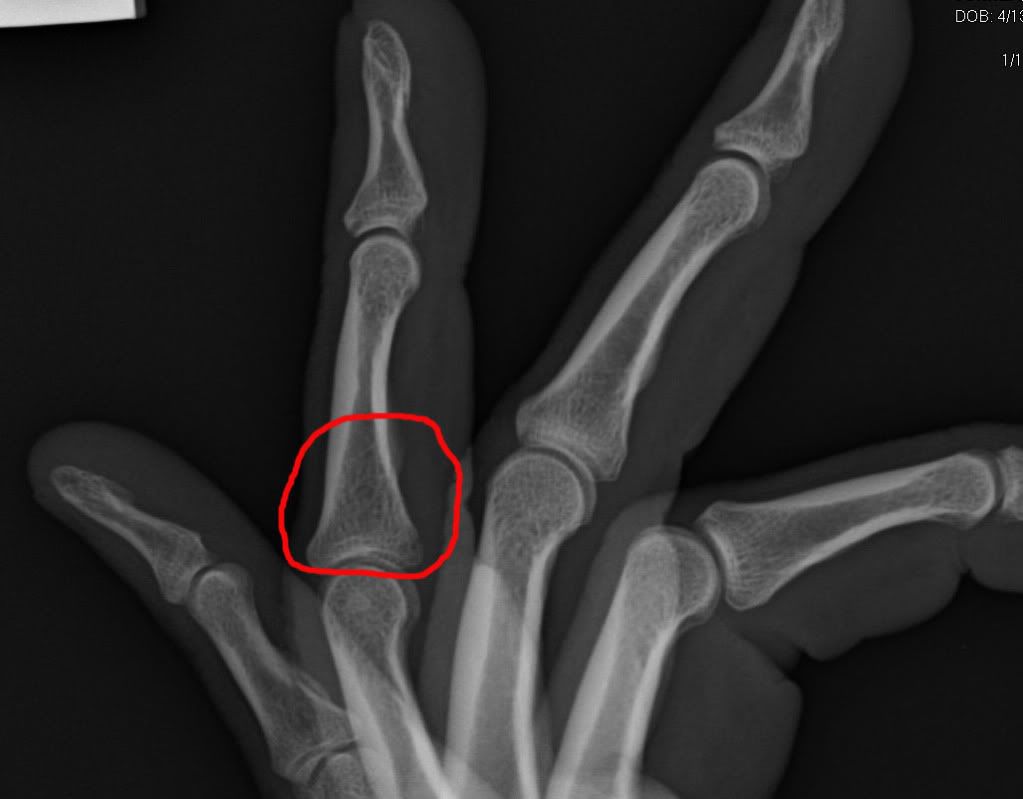

Well I joined the injury club last night. Was wrapping up a piece of cocktail glass for shipment when I dropped the roll of shrinkwrap. Well in my infinite wisdom I did not want it to slam into my kitchen floor, so I went to grab the falling roll. As I went to grab it the roll slammed into my foot and a millisecond later my hand smashed into the top of the roll. After wailing in pain and almost passing out I finally took my sock off to see what I had done. Ripped the top skin right off the big toe and blood, but not bleeding too bad. So I was starting to think it was just a skin abrasion. After about a half hour I told the wife to drive me to the immediate care center. Was a good choice because after 2hrs there I limped out with a broken toe and a broken finger, both on my left side.

I tried to get the xray pics posted but the software they game me with them only allows me to view it. I am off work today so I will play around with it some more.